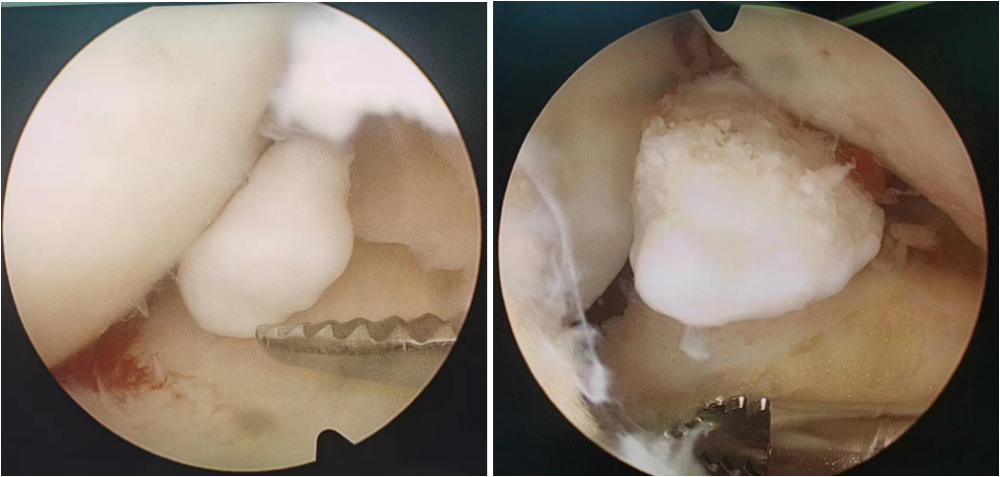

膝关节髁间窝游离体关节镜图

关节镜下的关节游离体